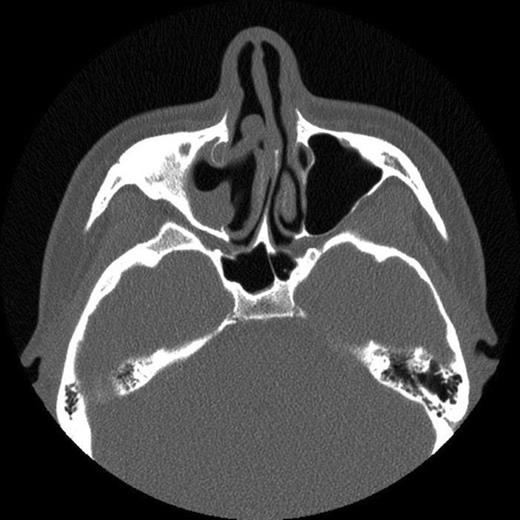

The patient then attended our clinic. Clinical examination and subsequent naso-endoscopy showed evidence of a right sided nasal obstruction with polypoidal mass within the nasal cavity. The patient underwent CT scan sinuses, which showed a well demarcated air defect in the extensively thickened sinus mucosa with large polypoidal mass. Evidence of entry of the cue was seen as a defect in the anterolateral wall of the right maxillary sinus and absent upper medial wall. No FB was seen.

CT scan showing fracture of the anterolateral wall of the right maxillary sinus and absent upper medial wall

The history and CT scan results suggest that following penetration of the snooker cue into the gingivo-labial sulcus it had broken through the right anterolateral maxillary wall and upper medial wall. On withdrawal of the snooker cue, the cue tip had broken off in the maxillary sinus. The FB had then caused localised inflammation resulting in episodes of sinusitis and facial pain. The FB had subsequently been discharged during a coughing episode 12 years later.